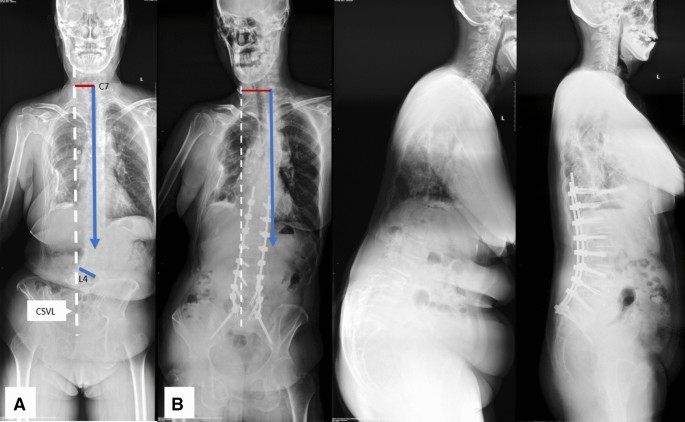

According to the relationship between orientation of L4 coronal tilt and C7 PL preoperatively, coronal patterns were subdivided into: 1, coronal consistency pattern, L4 coronally tilts toward the C7 PL (Fig. 1A); 2, coronal opposition pattern, L4 coronally tilts opposite the C7 PL (Fig. 2A).

Coronal consistency pattern (A). A 67-year-old female with coronal consistency pattern obtained worsening coronal imbalance after surgery (B). GCM changed from 44.8 mm preoperatively (A) to 58.7 mm postoperatively (B), with C7 plumb line on the same side (left) of CSVL. CSVL central sacral vertical line, GCM global coronal malalignment.

Different from mechanisms of postoperative coronal imbalance in degenerative lumbar scoliosis with different preoperative coronal curve types provided by Bao et al.2, who believed that asymmetrical osteotomy combined with compression technique on the convex side of the major curve might be the cause, the different surgical outcomes in patients with different preoperative coronal patterns might be due to their different inherent characteristics, regardless of what osteotomy techniques or compression/distraction maneuvers used. In patients with coronal consistency pattern, the orientation of L4 coronal tilt and C7 PL are on the same side of CSVL (Fig. 1A), while the orientation of L4 coronal tilt and C7 PL are on the different side of CSVL in patients with coronal opposition pattern (Fig. 2A). Thus, when a correction surgery is to be performed in patients with coronal consistency pattern, both coronal horizontalization of L4 (lumbosacral fractional curve) and the satisfactory correction of lumbar major curve should be obtained to achieve coronal balance. Otherwise, if either correction of lumbosacral fractional curve or the correction of lumbar major curve is not satisfactory, the coronal imbalance of whole spine might be left in existence (Fig. 1A,B). This might explain why patients with coronal consistency pattern carried greater risk for postoperative coronal imbalance. On the contrary, for patients with coronal opposition pattern, the orientation of L4 coronal tilt and C7 plumb line are on the different side of CSVL. This feature of coronal opposition pattern makes it much easier to correct global coronal malalignment (Fig. 2A,B). This hypothesis was supported by our clinical experience.

In our clinical practice, we found that it was easy to correct the global coronal malalignment in patients with coronal opposition pattern, there were 11 out of 40 cases with whose C7 PL were corrected from one side (right or left) of CSVL preoperatively to the opposite side (left or right) of CSVL postoperatively (Fig. 2A,B). Furthermore, three of which were overcorrected from preoperative coronal imbalance with C7 PL on one side of CSVL to postoperative coronal imbalance with C7 PL on the opposite side of CSVL. During surgery, caution must be taken to avoid overcorrection of global coronal malalignment in patients with coronal opposition pattern. On the contrary, for patients with coronal consistency pattern, it is more difficult to correct the global coronal malalignment. Patients with consistency pattern were more prone to under-correction and left coronal imbalance in existence or even worsening the coronal imbalance on the same side of CSVL as preoperatively (Fig. 1A,B).